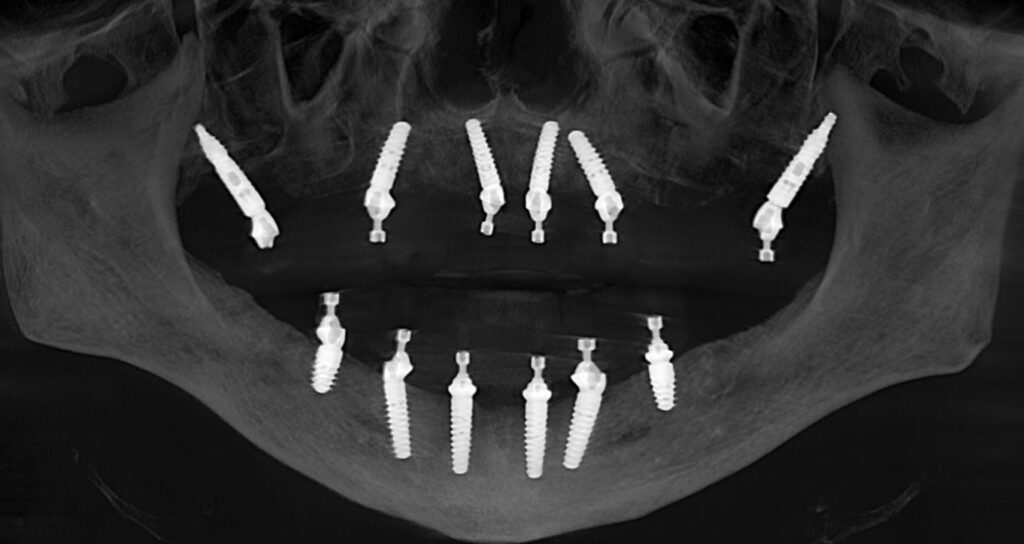

Implant Placement

Using precise, guided surgical protocols, implants are placed to create a strong, stable foundation for the full-arch restoration.